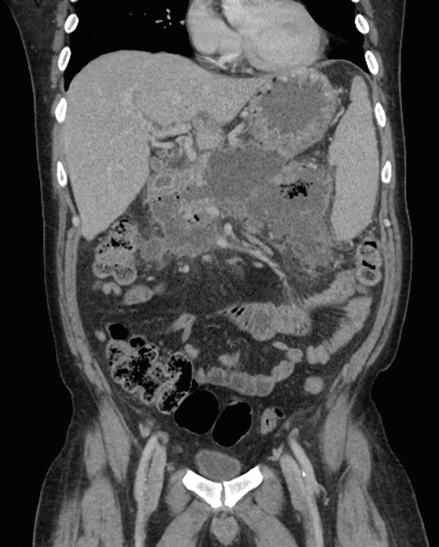

Figure 7.1

CT scan of the abdomen with extensive pancreatic necrosis, with a large amount of peripancreatic edema and several poorly organized fluid collections, the largest measuring 5.7 cm × 2 cm × 2.7 cm